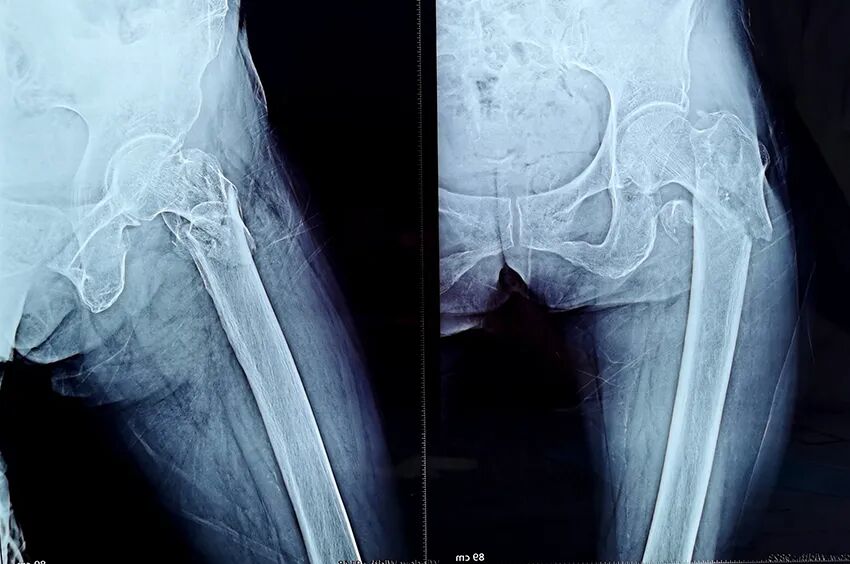

患者陈某,女性,今年88岁,家住廉江新民镇某村。

入院:2022年10月1日;出院:2022年10月19日。

术前图像

术后图像